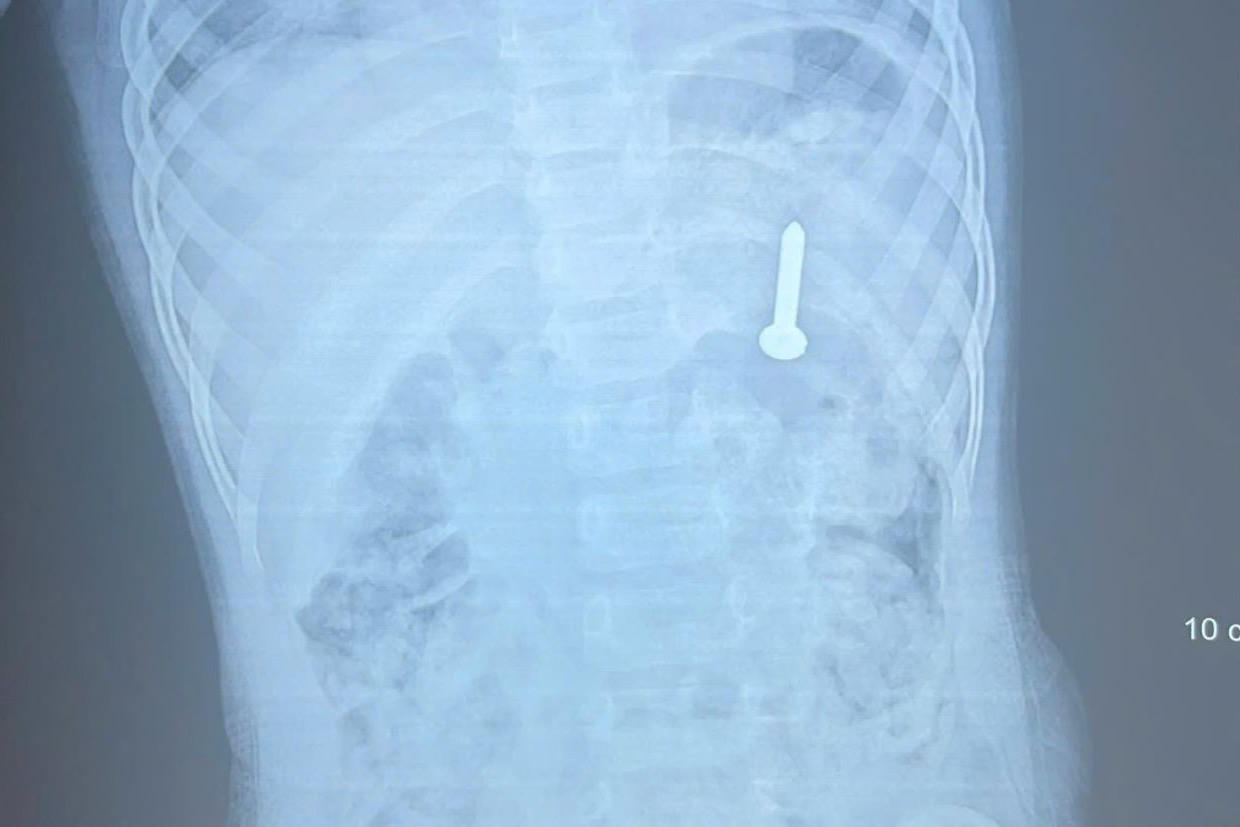

Chiếc đinh vít được phát hiện qua phim X-quang của bệnh nhi.

(PLVN) - Ngày 14/4, Bệnh viện Đa khoa tỉnh Quảng Trị cho biết, đơn vị vừa tiếp nhận và xử trí thành công một trường hợp bệnh nhi nuốt dị vật nguy hiểm là đinh vít dài 2,5cm.

Qua thăm khám và chụp X-quang, các bác sĩ xác định dị vật đã nằm trong dạ dày, tiềm ẩn nguy cơ gây thủng đường tiêu hóa và xuất huyết nghiêm trọng nếu không được can thiệp kịp thời.